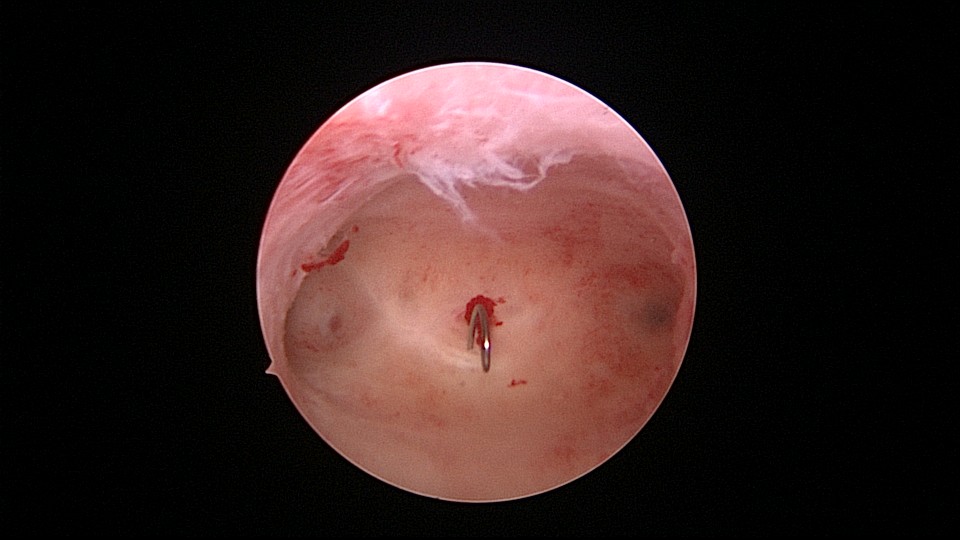

患者53岁,G3P1,顺产1次(产后大出血)。1年前因盆腔器官脱垂行阴道前后壁修补手术,同时行宫腔镜息肉切除手术,病检为增生反应子宫内膜伴出血。2025年2月,绝经2年,阴道出血半天,行宫腔镜检查及诊刮,放置曼月乐并固定,用曼月乐尾丝连接环与不锈钢挂钩,将挂钩插入宫底肌层固定,异物钳原位固定曼月乐,退出宫腔镜,结束手术。2025年4月复查B超曼月乐位置正常,环顶端距宫底1.1cm。病检为子宫内膜增生,不伴非典型增生。